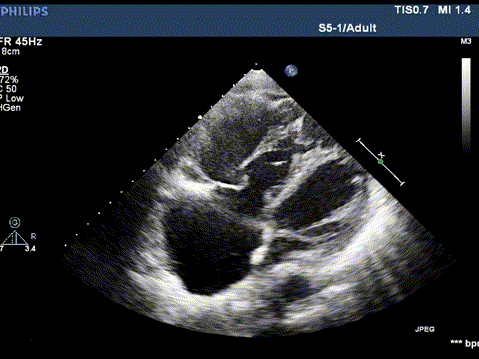

图片

术前心超

房间隔没有血流

术后心超

心房间可见分流束